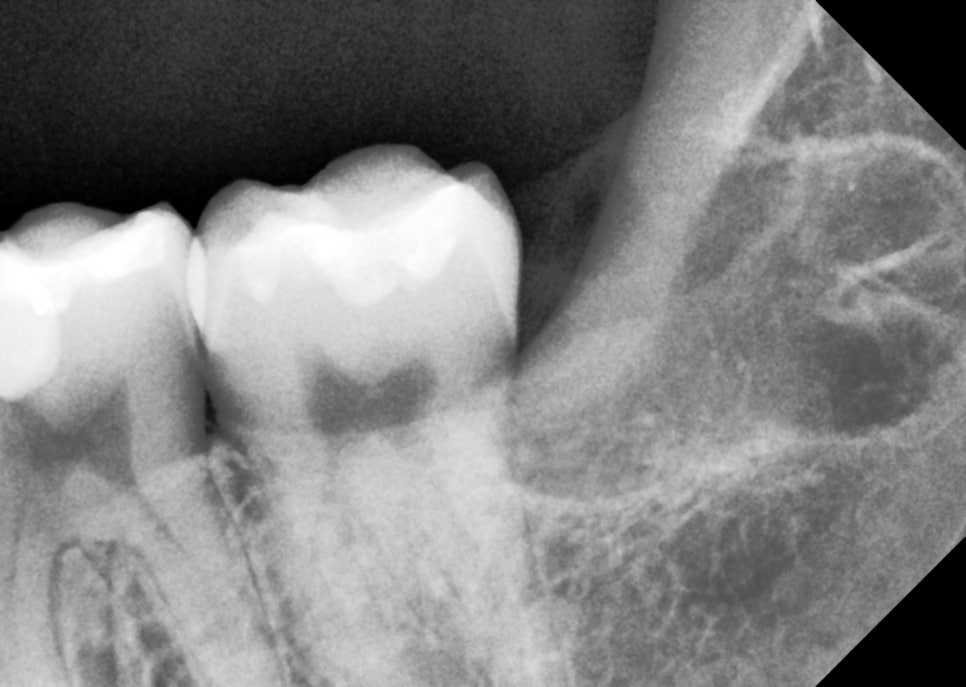

뿌리와 엑스레이를 보면서 잘 나온 것 같았지만, 더블 체크를 위해 엑스레이를 촬영했어요.

촬영일 : 251121

깔끔하게 제거된 것을 볼 수 있었어요.